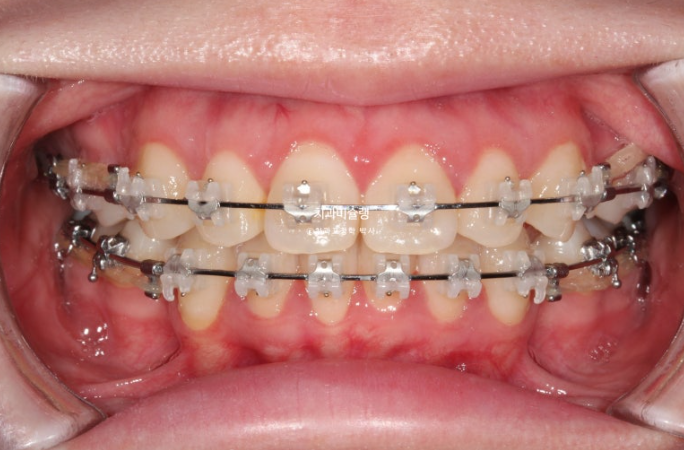

23년 8월 교정치료를 위해 내원한 환자분입니다.

23.08

위 아래 중심선은 어긋나 있고

윗니가 아랫니를 많이 덮어 아랫니가 잘 안보이는 심한 과개교합이 보입니다.

파란 화살표 부분은 위 아래 큰어금니가 엇갈려 물리는 가위교합입니다.

파란화살표 두번째 큰어금니가 바깥으로 밀려나가 가위교합이 된 것 입니다.

앞니도 많이 삐뚤합니다.